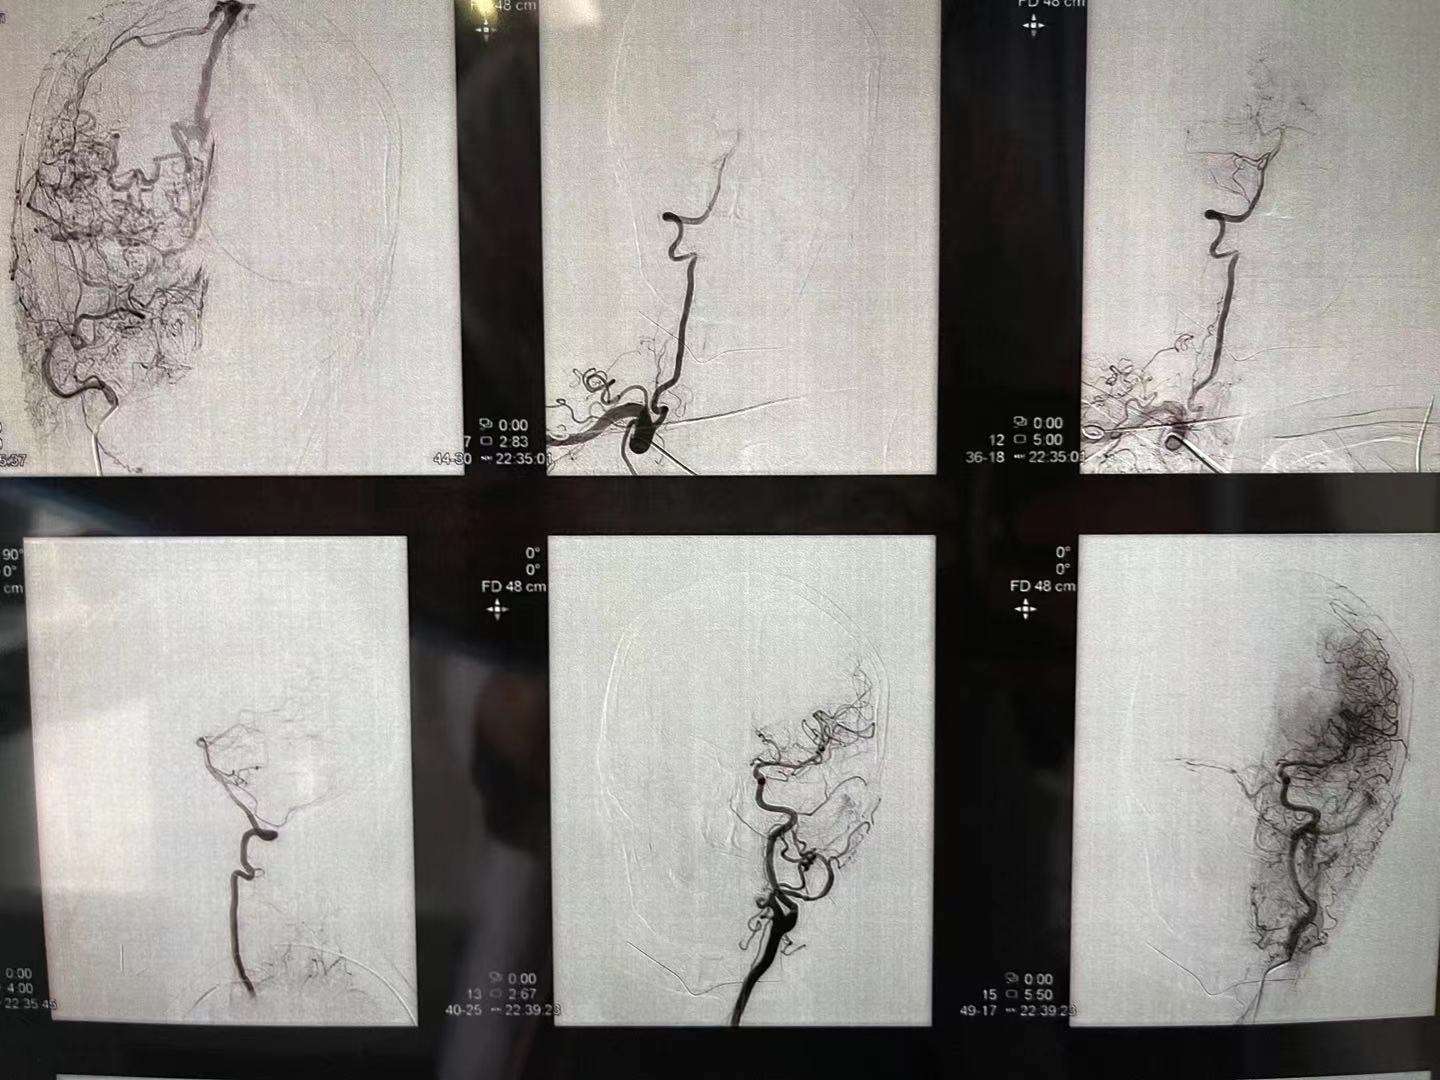

术后,清爽了,瘘口都不在显影,

不减影,看看胶

硬脑膜动静脉瘘介入栓塞术后

术后,清爽了,瘘口都不在显影,

不减影,看看胶